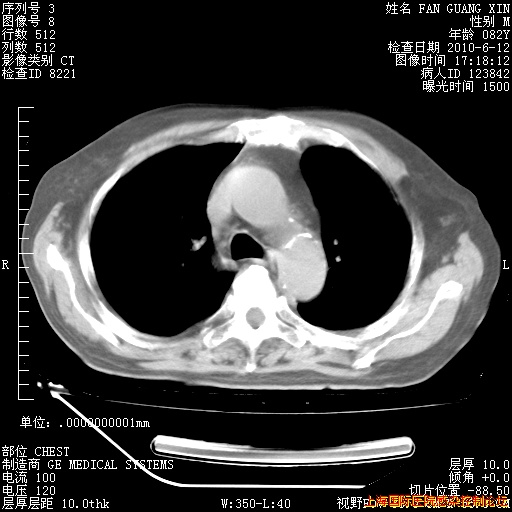

6月12日纵膈窗

整整相隔30天的肺部CT好像有所好转啊。甲强龙减量第3天,需要观察体温。